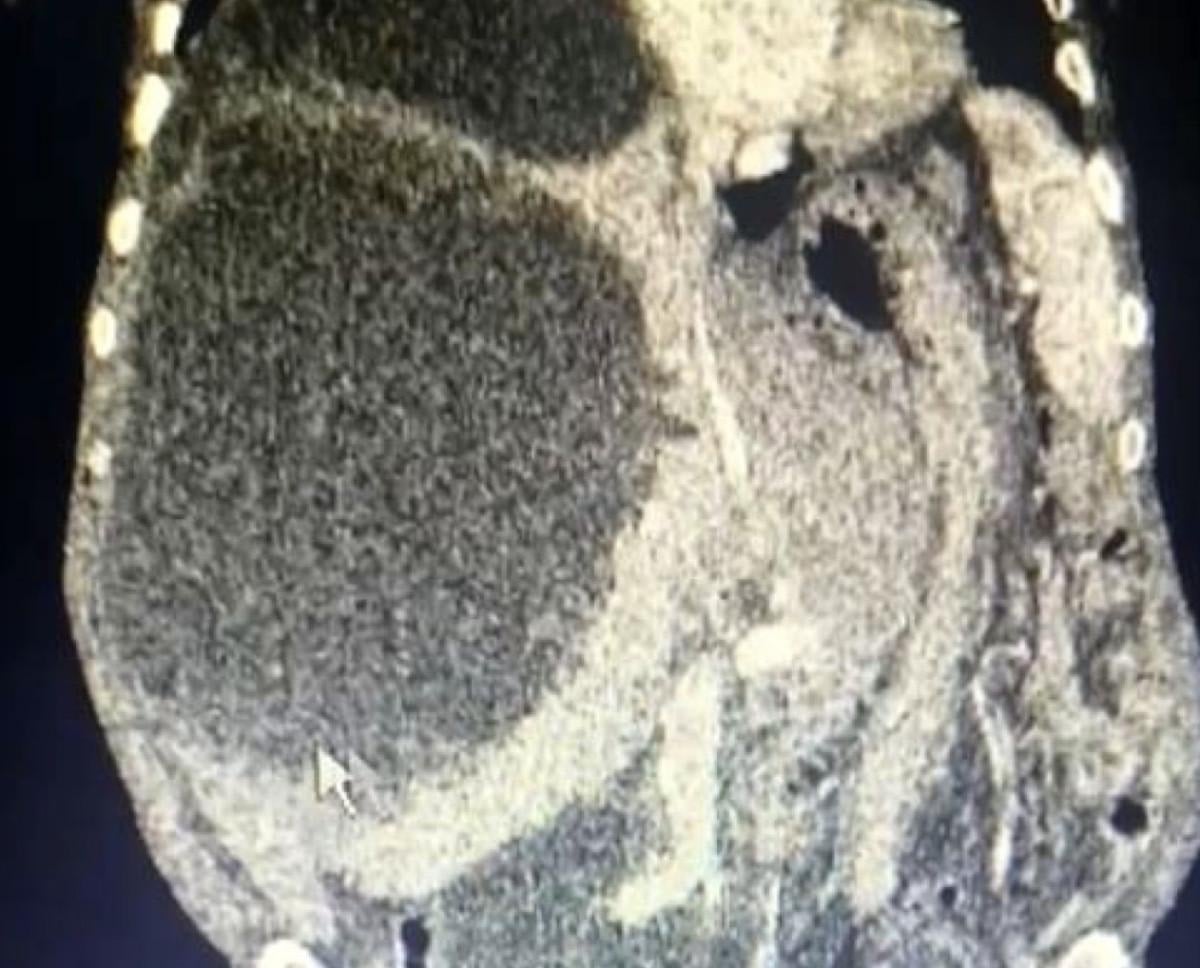

Taşdelen’e sağlık görevlileri tarafından yapılan muayene ve görüntüleme tetkiklerinde karaciğerinde, 90 santimetreye ulaşarak karnını kaplayan 3 ayrı kedi-köpek kisti saptandı.

Dünya literatüründe 90 santimetreye ulaşarak tüm karnı dolduran bir kist ile ilk kez karşılaşıldığını ifade eden Dr. Çelik, kedi-köpek kisti olarak bilinen hastalığın bulaşma yollarını anlattı.

O hastalıkları ekarte edebilmek için ilgili branşlarla birlikte vakayı değerlendirdik. Hastamızın ameliyat olabilirliğini tartıştık. Konsey kararı ile ameliyatına karar verdik. Hastamızın karaciğerinde 3 ayrı kist vardı. Tüm karnı kist ile kaplıydı. 2 tanesinin tamamına çıkardık. Diğerini ise kontrole alarak içini boşalttık.

Dünya literatüründe 90 santimetreye ulaşarak tüm karnı dolduran kist görmedik. Ameliyatımız 2 saat sürdü. Hastamızın safra yolları kontrol edildi. Hastamızın durumu gayet iyi. Solunum cihazından bağımsız olarak kendi başına solunum yapabiliyor. Yarın da servise alacağız.